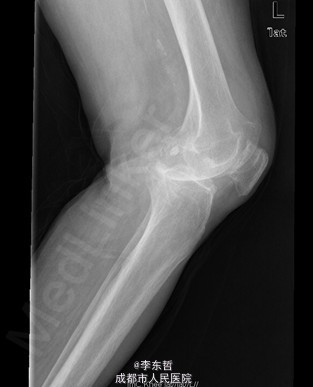

患者女,74岁,因“双膝疼痛20年,加重伴行走困难8年”入院。患者诉20年前开始出现双膝关节疼痛,负重行走、下楼时疼痛加重,休息后可缓解,尚可下蹲。自行购买止痛药口服,关节腔内注射玻璃酸钠、理疗等处理,疼痛时有缓解。但症状反复发作。8年前疼痛加重且行走困难,扶拐行走仅能坚持约10余米,上下楼梯艰难,下蹲不能,以左侧为重。遂来院就诊。

查体:跛行步态,双膝关节屈曲内翻畸形,双膝内侧间隙压痛,双膝髌股关节间隙压痛,左膝伸-20°,屈110°内翻10°。右膝伸-20°,屈110°内翻10°,双膝屈伸活动时髌骨下摩擦感(+)。 辅助检查:X片示双侧髌股关节内侧间室变窄,关节边缘骨赘增生,软骨下骨硬化。